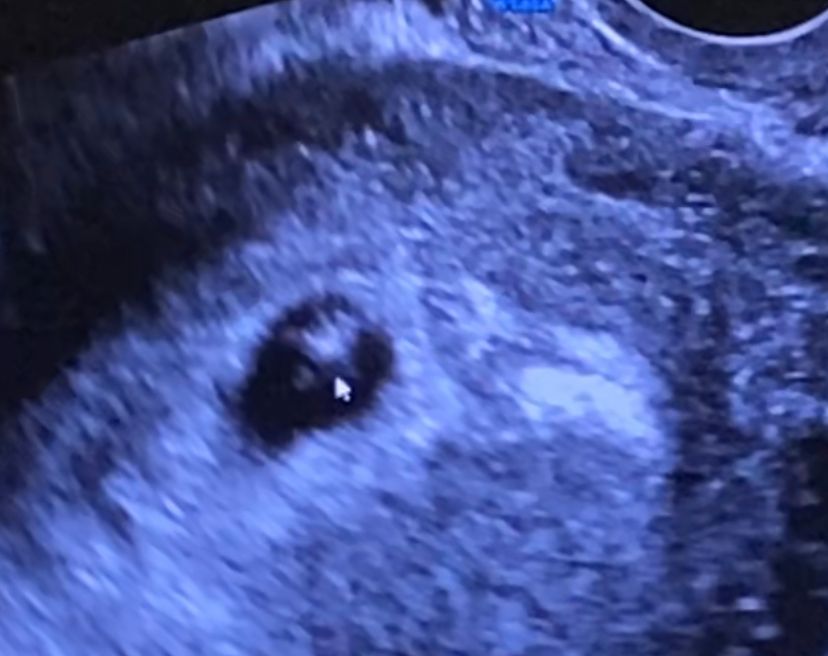

Узи 28 дпп